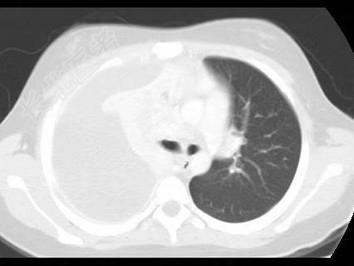

- 单项选择题下列图像最佳诊断是什么 ( )

A、脓胸

B、气胸

C、肺不张

D、肺癌

E、肺结核